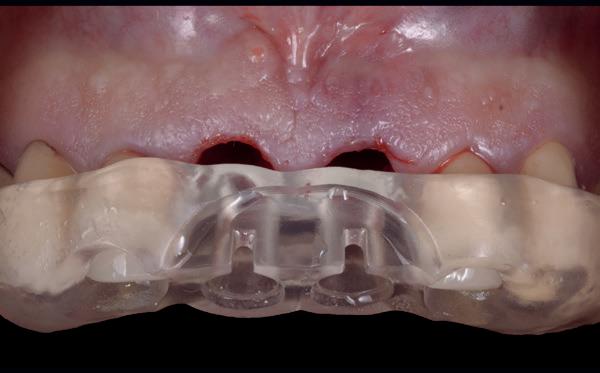

Zitting 4 plaatsen PMMA brug & multi-unit abutments

Wanneer de tijdelijke brug retour komt, dienen eerst de healing abutments verwijderd te worden en de implantaten uitgespoeld te worden met Blue M spoelmiddel in een monoject. De brug paste niet direct op de interne verbindingen van de implantaten, omdat deze daarvoor niet parallel genoeg stonden, omdat de kaak in een curve liep. Daarom wordt over het algemeen gekozen voor multi-unit abutments die op de implantaten worden gedraaid. Hierdoor wordt de brug op coronaal hoger niveau geplaatst en door de multi-unit abutments wordt een open inzetrichting verkregen.

De PMMA tijdelijke brug werd direct op de multi-unit abutments geschroefd met kleine schroefjes. De schroefgaten van de brug werden afgesloten met teflontape en composiet. Indien nodig, kon er aan de PMMA brug de occlusie en articulatie geslepen worden. In deze casus was dat verder niet nodig. De

patiënt kon 2 maanden functioneren met de tijdelijke brug, waarna een kort consult werd gepland om te bespreken of hij tevreden was met de esthetiek en functie. Voor de patiënt hoefde niks veranderd te worden (afbeelding 11-14).

11. Tijdelijke PMMA-brug op model

12. Na plaatsen van multi-unit abutments

13. Na plaatsen tijdelijke brug op de implantaten

14. Portretfoto met tijdelijke brug